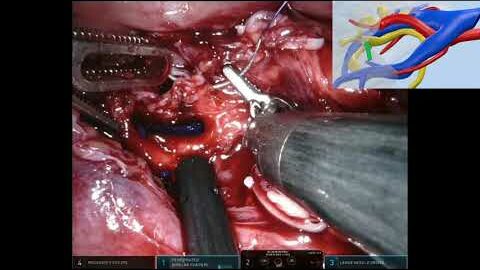

#332 First-in-man AI-assisted Augmented Reality Surgery Drs. Alex Mottrie & Jasper Hofman